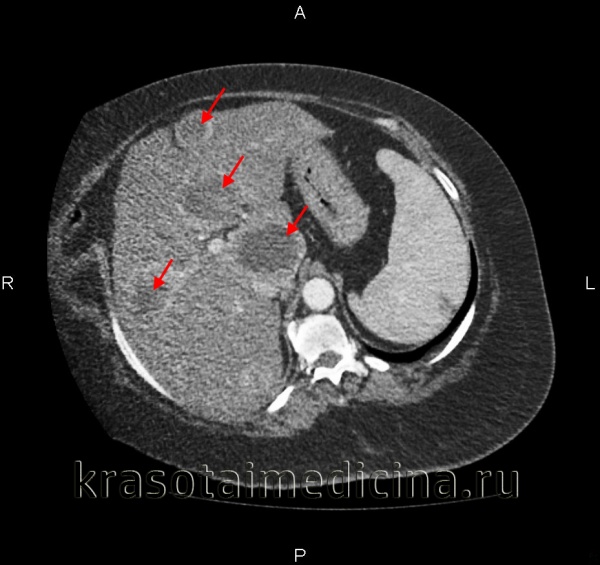

КТ органов брюшной полости. Множественные вторичные опухоли печени (первичная опухоль – рак молочной железы)

Для более точной диагностики прибегают к проведению ультразвукового сканирования, компьютерной томографии, МРТ печени, ангиографии печени. С целью гистологической верификации образования проводится пункционная биопсия печени или диагностическая лапароскопия.

При признаках метастатического поражения печени необходимо установление локализации первичной опухоли, для чего может потребоваться выполнение рентгенографии желудка, ЭГДС, маммографии, УЗИ молочных желез, колоноскопии, ирригоскопии, рентгенографии легких и т. д.